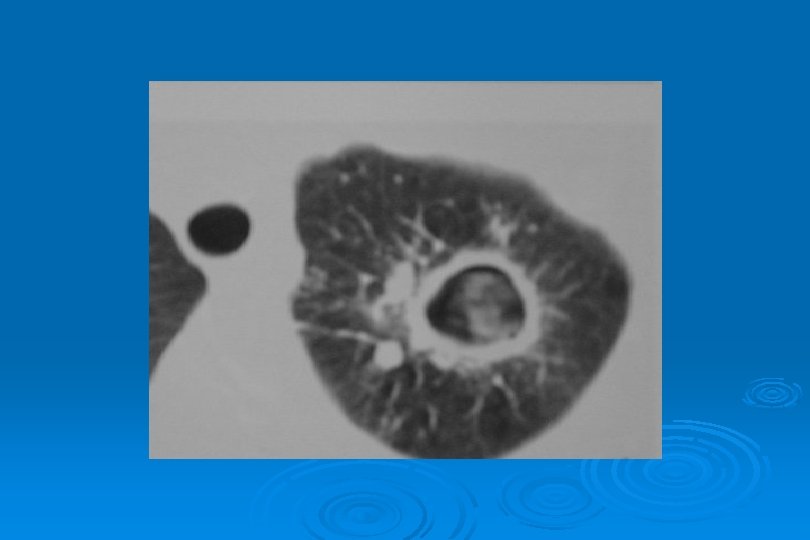

MİÇETOMA Aspergilloma veya mantar topu da denir Ø Mantar, fibrin, mukus ve hücre döküntülerinden oluşmuş kitlenin tüberküloz kavitesi, kist veya kistik bronşektazi içinde yerleşmesidir Ø Duvarı erode ederek % 50 -80 olguda hemoptiziye yol açar Ø Bir kavite içerisinde kavite duvarından ay şeklinde radyolusen bir bant ile ayrılan homojen iç yapıda yuvarlak veya oval kitle Ø

MİÇETOMA Ø Kavite ince duvarlı olup hava-sıvı seviyesi içermez Ø BT’de mantar topunun nonhomojen olduğu, içinde hava odaklarının bulunduğu, yüzüstü ve sırt üstü alınan kesitlerde yer değiştirmesi nedeniyle tanısı kolayca konur